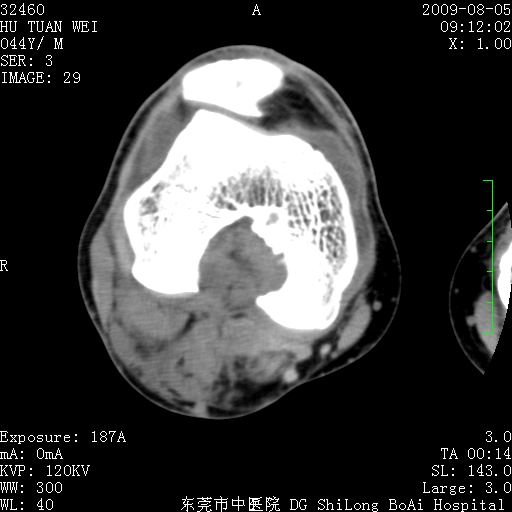

中年男性,膝韧带损伤术前检查!其他病史不清粗,不是我接手病人、且出院了!

1、股骨下段囊状膨胀性病变,边缘硬化明显,内多个残留骨棘呈多房型改变,囊腔密度较高无钙化,膝关节滑膜囊增厚,密度增高,关节腔少量积液。考虑:邻关节囊肿、退变性囊肿(软骨下囊肿)、着色性绒毛结节性滑膜炎、abc、骨巨、良性纤维组织细胞瘤等鉴。虽然年龄偏大,部位于骨端,但有外伤史,本人还是倾向于动脉瘤样骨囊肿(abc)可能性大。邻关节囊肿及软骨下囊肿次之考虑。

2、胫骨髁间棘撕脱骨折,交叉韧带损伤可能;

3、关节退行性改变。

病理结果:色素沉着绒毛结节性滑膜炎

感谢反馈病理结果!本病为慢性关节病变。以关节滑膜高度增生、绒毛结节形成伴含铁血黄素趁着为特点。病因:有炎症、肿瘤、外伤关节出血、代谢障碍、变态反应及感染等学说。增强扫描呈关节腔内单个或多个强化的软组织结节影或滑膜不规则增厚伴关节积液为本病的特征性表现。